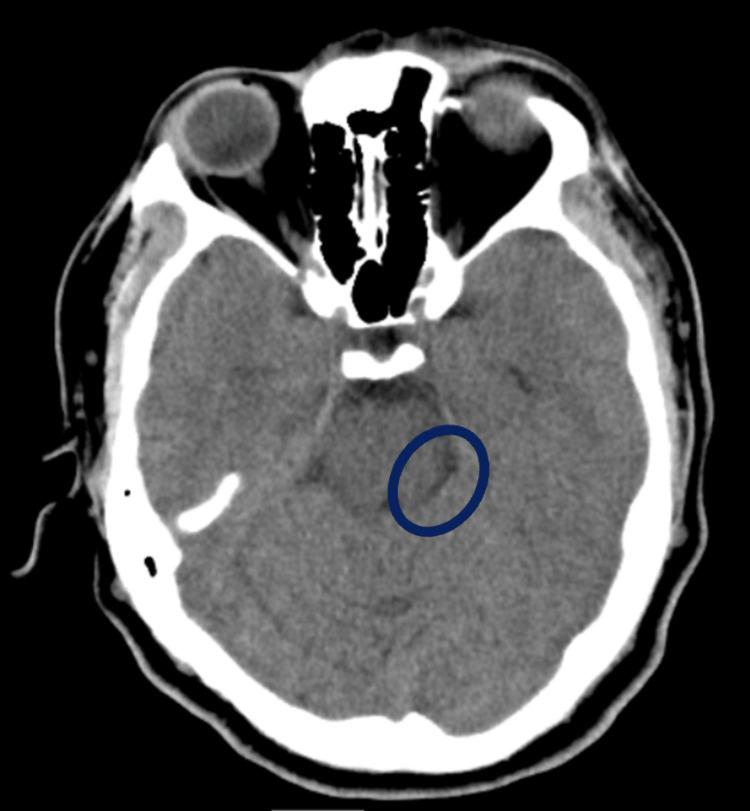

Valvular heart disease (VHD) occurs when there is a functional impairment in the valvular apparatus that either obstructs or regurgitates the backflow of blood. When a microorganism resides in those valves, it injures the leaflets and causes complications such as thromboembolic events. Infective endocarditis (IE), usually caused by the Staphylococci and Streptococcus group, is a disease that occurs on the heart valves. Antibiotic resistance is common; thus, culture and sensitivity testing should be done for a more targeted treatment approach. We herein present a rare case of () vegetations found in a patient's heart that initially presented with cerebrovascular disease symptoms and underwent heart surgery in the end.

当心脏瓣膜装置出现功能障碍,导致血液流动受阻或反流时,就会发生心脏瓣膜病(VHD)。当微生物寄生于这些瓣膜时,会损伤瓣叶并引发血栓栓塞事件等并发症。感染性心内膜炎(IE)通常由葡萄球菌和链球菌引起,是一种发生在心脏瓣膜上的疾病。抗生素耐药性很常见;因此,应进行培养和药敏试验,以采取更有针对性的治疗方法。我们在此报告一例罕见病例,患者心脏发现有()赘生物,最初表现为脑血管疾病症状,最终接受了心脏手术。